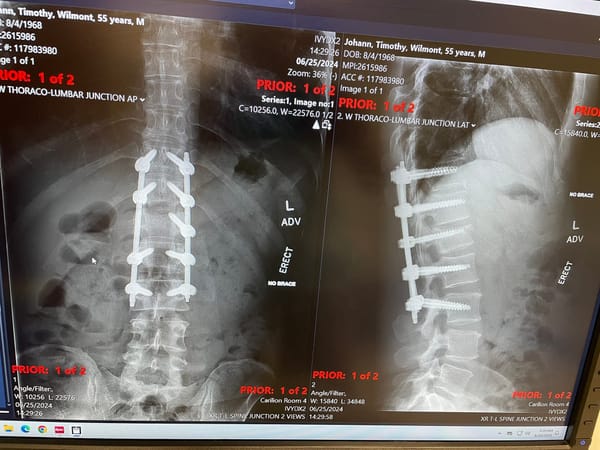

Before and after photos, and some other updates